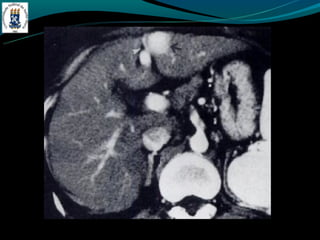

Peliose hepática